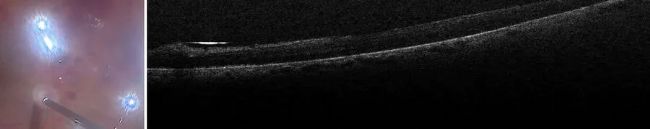

增生性糖尿病視網膜病變是光學相干斷層掃描的主要應用領域之一,包括術前應用。即使在使用染料的情況下,該技術也能準確顯示膜支架的區域。這樣,外科醫生就能看到用鑷子夾住薄膜的縫隙,而不會對薄膜下方的視網膜造成損傷(圖 2)。

圖 2:術中 OCT 幫助觀察到用鑷子夾住薄膜的縫隙,同時不會對視網膜造成損傷。圖片由 Nikolaos Bechrakis 教授提供。

在這個病例中,剝離眼膜后,由于眼球內有空氣,出現了氣泡反射(圖 3)。通過術中 OCT,可以看到視網膜的氣場情況。這樣就可以看到視網膜下有多少液體,并檢查是否有殘留的眼膜。

圖 3:術中使用 OCT 可以看到視網膜下有多少積液,并檢查剝離后是否有殘留的薄膜。圖片由 Nikolaos Bechrakis 教授提供。